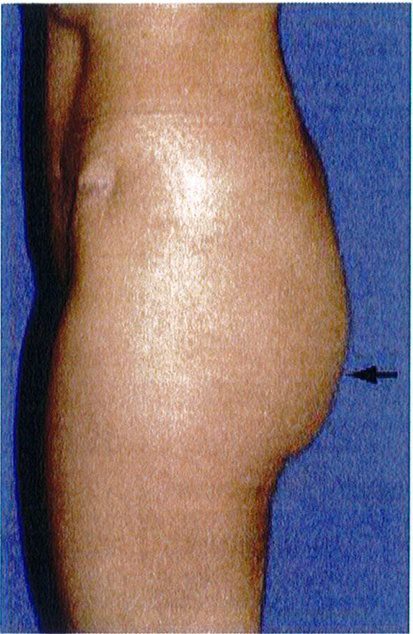

Mặt bên vùng mông có thế được chia thành 3 vùng: trên, giữa, dưới (xem hình 19). Sự phân chia tương ứng với 3 điểm A, B, C và chúng giúp xác định vùng nào được phân bố mỡ nhiều/ít hơn các vùng còn lại. Trong thấm mỹ vùng mông, phần lớn mô mỡ dưới da sẽ nằm ở vùng trung tâm (chính giữa mông), và phần mỡ dưới da còn lại sẽ được phân bố đồng đều ở hai bên. Như vậy chúng ta có thể tưởng tượng ra hình dạng tổng thể của mông khi nhìn từ phía bên là hính chữ C ngược (Hình 19). Có một số tác giả cho rằng điểm nhô ra nhiều nhất của vùng mông sẽ là điểm nằm ngang với xương mu ở tư thế đứng.

Khi làm việc từ góc nhìn bên này, chúng ta cần rõ ràng xác định được đâu là ranh giới vùng mông trên giữa dưới (Hình 20). Việc xác định này rất quan trọng nhằm

Hình. 19. Ba vùng trên giữa dưới của mông.

Hình. 20. Phần lớn thể tích vùng mông tập trung ở 1/3 dưới, giữa, trên.